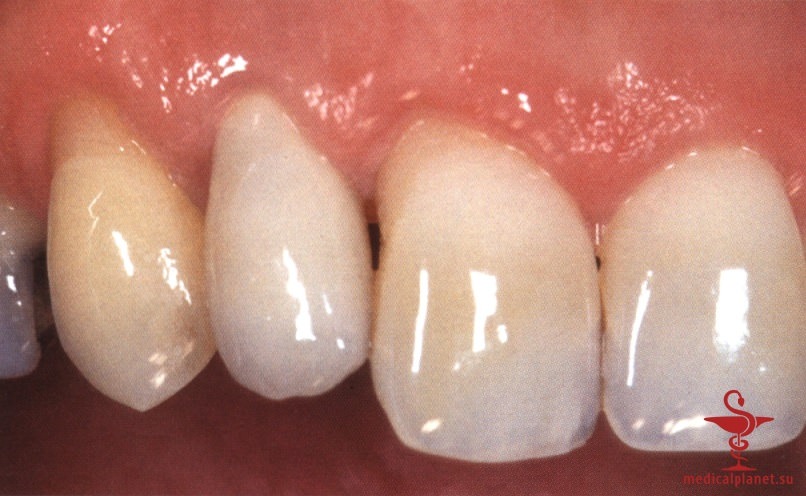

в) Отслаивание лоскута при одноэтапной имплантации. Одноэтапная немедленная имплантация кажется предпочтительной, поскольку герметичное ушивание раны сразу после удаления зуба представляется нецелесообразным. Вместо плотного сопоставления краев раны на имплантат немедленно фиксируют формирователь десны или временную реставрацию, что снижает риск деформации прилегающих мягких тканей.

Следует помнить, что любой, даже самый маленький лоскут требует наложения швов в области сосочков, а каждый разрез в этой зоне ведет к уменьшению их высоты, как обсуждалось в отдельной статье на сайте (просим Вас пользоваться формой поиска по сайту выше) (рис. 3). Иными словами, при немедленной имплантации в эстетически значимой зоне нужно избегать отслаивания лоскута.